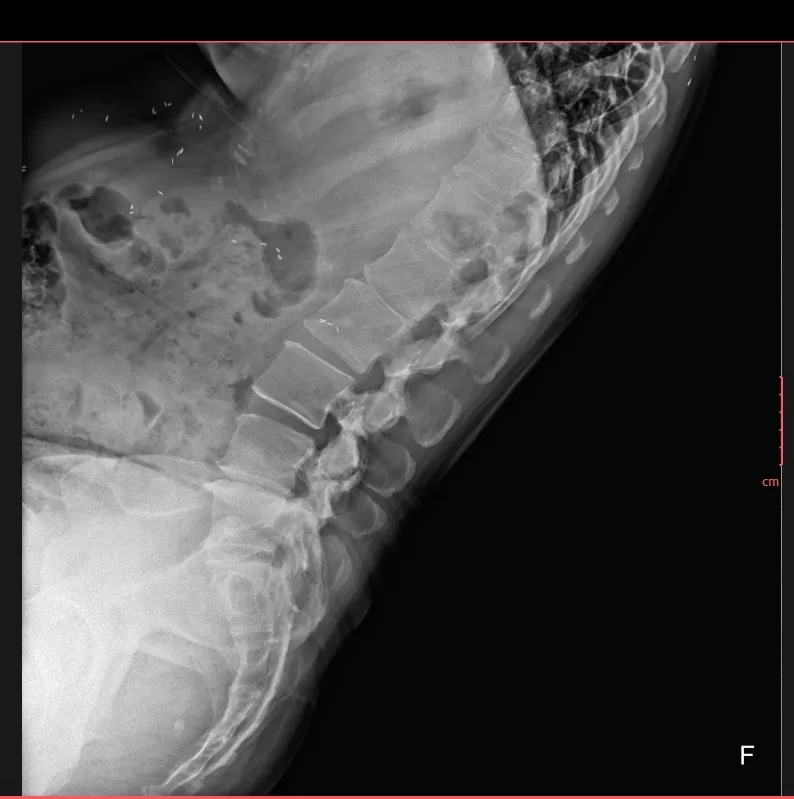

📸 Hình ảnh X-quang thường quy (đính kèm) cho thấy:

-

Nhiều nốt cản quang nhỏ, hình dạng thoi/hạt gạo,

Phân bố rải rác trong mô mềm và các khối cơ vùng ngực, bụng và thành bụng,

Các tổn thương không liên quan đến cấu trúc xương khớp.

➡️ Đây là hình ảnh điển hình gợi ý nhiễm ký sinh trùng dạng kén, đặc biệt là kén sán, một bệnh lý dễ bị chẩn đoán nhầm do triệu chứng lâm sàng không đặc hiệu.